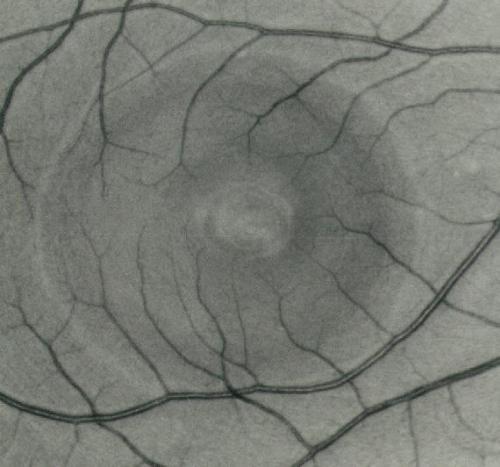

chriorétinopathie sereuse centrale

crsc3.jpg